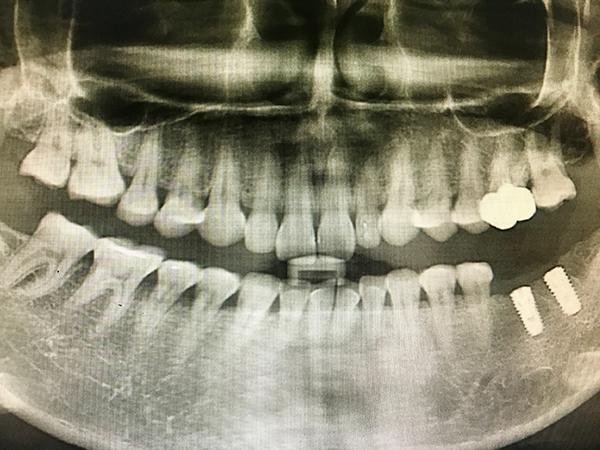

임플란트 치료 기간의 가장 중요한 포인트는 바로 잇몸뼈의 여부입니다. 만약 잇몸뼈가 충분하다면 일반적으로 3~4개월 정도면 충분할 수 있는데, 잇몸뼈가 부족하다면 뼈이식을 해야 하므로 기간이 더 길어질 수 있습니다. 잇몸뼈가 부족한 경우 뼈이식 수술을 통해 잇몸뼈를 보강해야 하며, 이는 임플란트 치료 기간을 6개월 이상으로 연장할 수 있습니다. 따라서 초기 상담 시 잇몸뼈 상태를 정확히 진단받는 것이 중요합니다.

또한, 임플란트의 위치에 따라 치료 기간이 달라지는데, 상악의 경우엔 5개월 ~ 6개월 정도가 소요되고, 하악의 경우 3개월 ~ 4개월 정도가 소요되는 것이 일반적입니다. 하악은 상악에 비해 치조골의 밀도가 높다 보니 하악 쪽이 치료 기간이 더 단축되는 것입니다. 상악의 경우 부비동이 가까워 추가적인 뼈이식이 필요한 경우가 많아 치료 기간이 더 길어질 수 있습니다.

만약 임플란트를 해야 할 치아가 여러 개라면 치료 기간은 더 늘어날 수 있습니다. 또한, 당뇨나 골다공증 같은 전신질환을 가지고 있으면 회복이 더디거나 염증이 발생할 수 있어 치료 기간은 더 길어질 수 있습니다. 전신질환이 있는 환자는 치료 전 충분한 상담과 진단이 필요하며, 이에 따라 치료 계획이 수정될 수 있습니다.